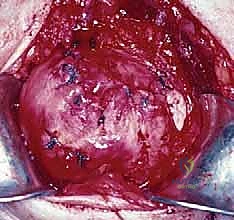

المرحلة الثالثة: زراعة الخطاطيف وخياطة الأوتار

يتم تحضير "بصمة الوتر" (Footprint) على رأس عظم العضد عن طريق تقشير العظم بلطف لتعزيز النزيف الخفيف الذي يجلب الخلايا الجذعية وعوامل النمو لتسريع التئام الوتر بالعظم.

ثم يتم زرع خطاطيف جراحية (Suture Anchors) متطورة (مصنوعة من التيتانيوم أو مواد قابلة للامتصاص) داخل العظم.

هذه الخطاطيف متصلة بخيوط جراحية فائقة القوة. يقوم الدكتور هطيف بتمرير هذه الخيوط عبر الوتر الممزق باستخدام تقنيات خياطة معقدة (مثل صف مزدوج Double Row) لضمان توزيع الضغط وتوفير تثبيت ميكانيكي صلب.

يتم ربط العقد الجراحية بإحكام، ويتم اختبار حركة الكتف على طاولة العمليات للتأكد من متانة الإصلاح وقدرة الوتر على تحمل الشد.

المرحلة الرابعة: الإغلاق